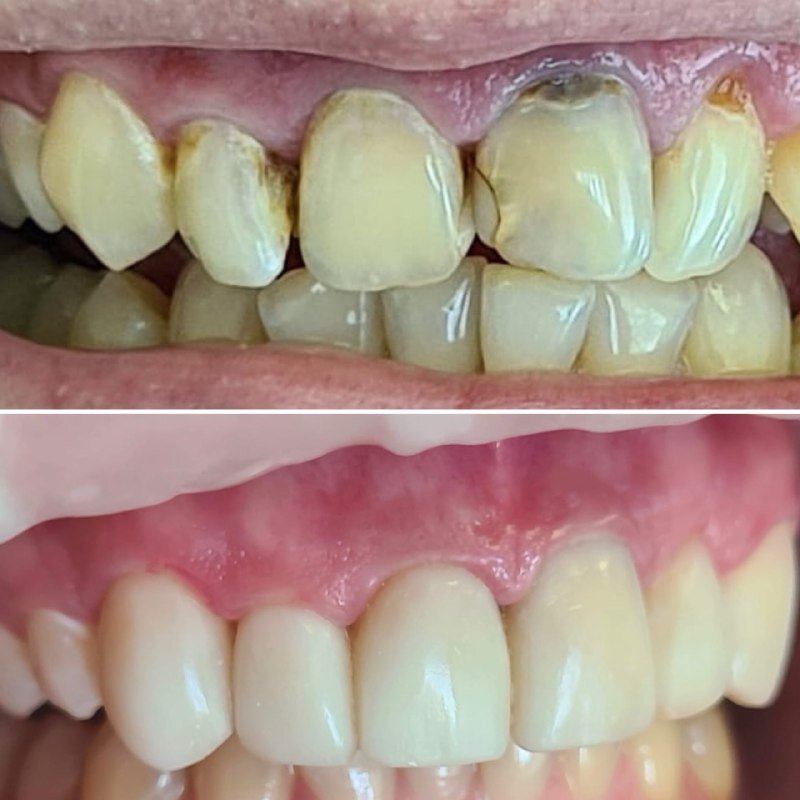

Фотогалерея